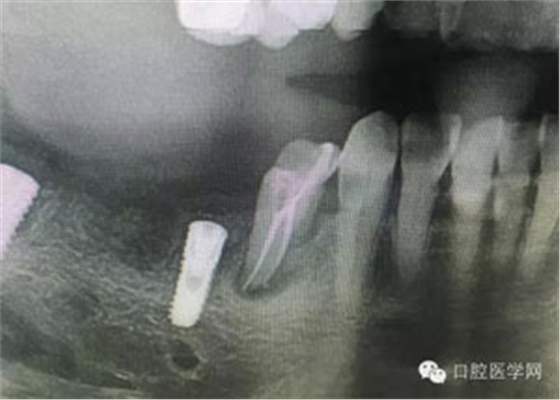

病例1:患者迫切希望保留自己的這一顆牙齒,根尖周陰影比較大,二度松動(dòng).而且旁邊有種植修復(fù)體,和患者溝通好后,治療好后觀察一個(gè)月后冠修復(fù),因?yàn)橛蟹N植的后期修復(fù),所以有了機(jī)會(huì)觀察,術(shù)后三個(gè)月和術(shù)后四個(gè)月,根尖恢復(fù)的還算不錯(cuò),希望能夠繼續(xù)觀察下去.這樣子的病例,做的時(shí)候我們一定要非常的小心,和患者要有充分的溝通以及不同科室的溝通然后決定怎么樣做比較好,假如就是出現(xiàn)了問題,到時(shí)候我們也比較好處理些,免得我們自己到時(shí)候不好收?qǐng)觥?/span> 病例2:364647中齲的樹脂充填,現(xiàn)在樹脂的充填材料非常之多,有些時(shí)候,我們感覺有了好的材料我們就可以做出好的修復(fù),可是這是在我們有扎實(shí)的基本功的基礎(chǔ)上的,我們可以沒有那么好的樹脂,那么多的顏色選擇,修復(fù)的那么的逼真,但是我們至少要恢復(fù)患者牙齒的功能,將腐質(zhì)去除干凈,薄壁弱尖消除掉,選擇好適應(yīng)癥,給患者以盡可能好的修復(fù)。 來源于KQ88